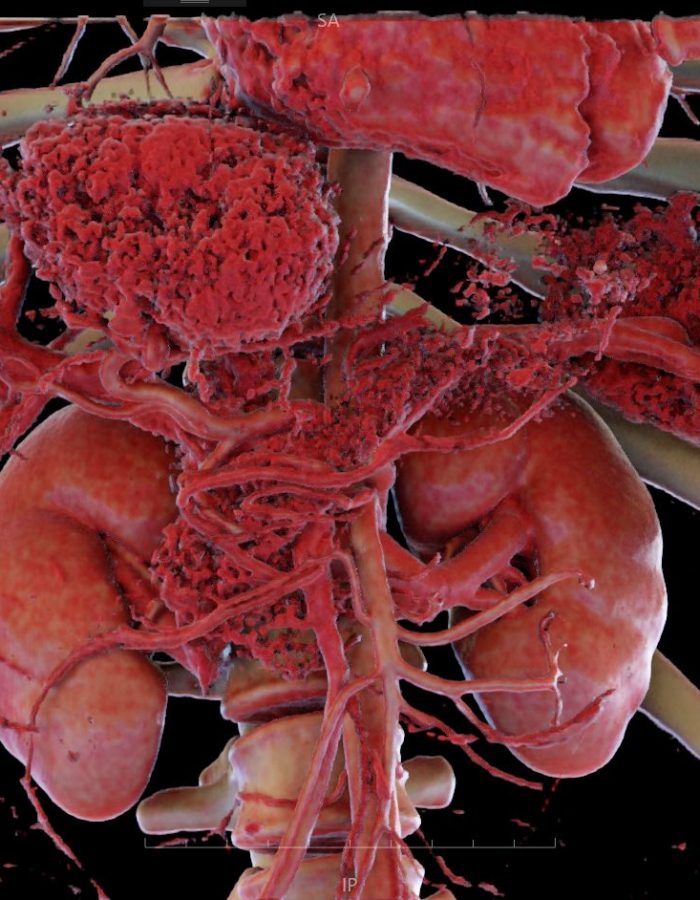

_ Amplia variedad de imágenes con un estilo profesional, tanto para estudios de casos pre operatorios como para estudio profundo de medicina.